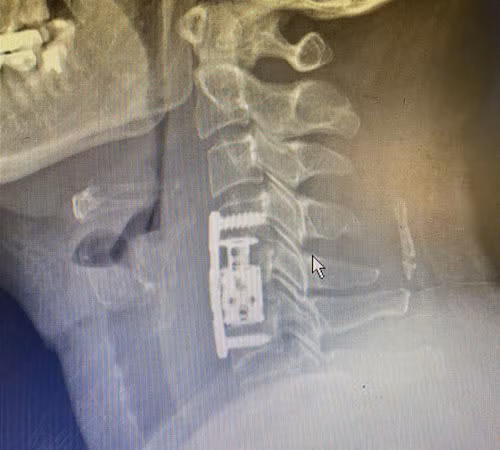

Đây là biểu hiện của hội chứng chèn ép tủy cổ gây ra. Trên phim chụp CT-Scanner, MRI cho thấy người bệnh bị thoát vị đốt sống cổ đoạn C4-C5, C5-C6, cốt hóa dây chằng dọc sau.

Sau khi hội chẩn và thống nhất, các bác sĩ tiến hành phẫu thuật thay thân đốt sống, lấy nhân đĩa đệm, đặt đốt sống nhân tạo đốt sống cổ, vít cố định đốt sống cổ cho người bệnh.

| Hình ảnh vùng đốt sống cổ của người bệnh sau khi được thay đốt sống cổ nhân tạo |